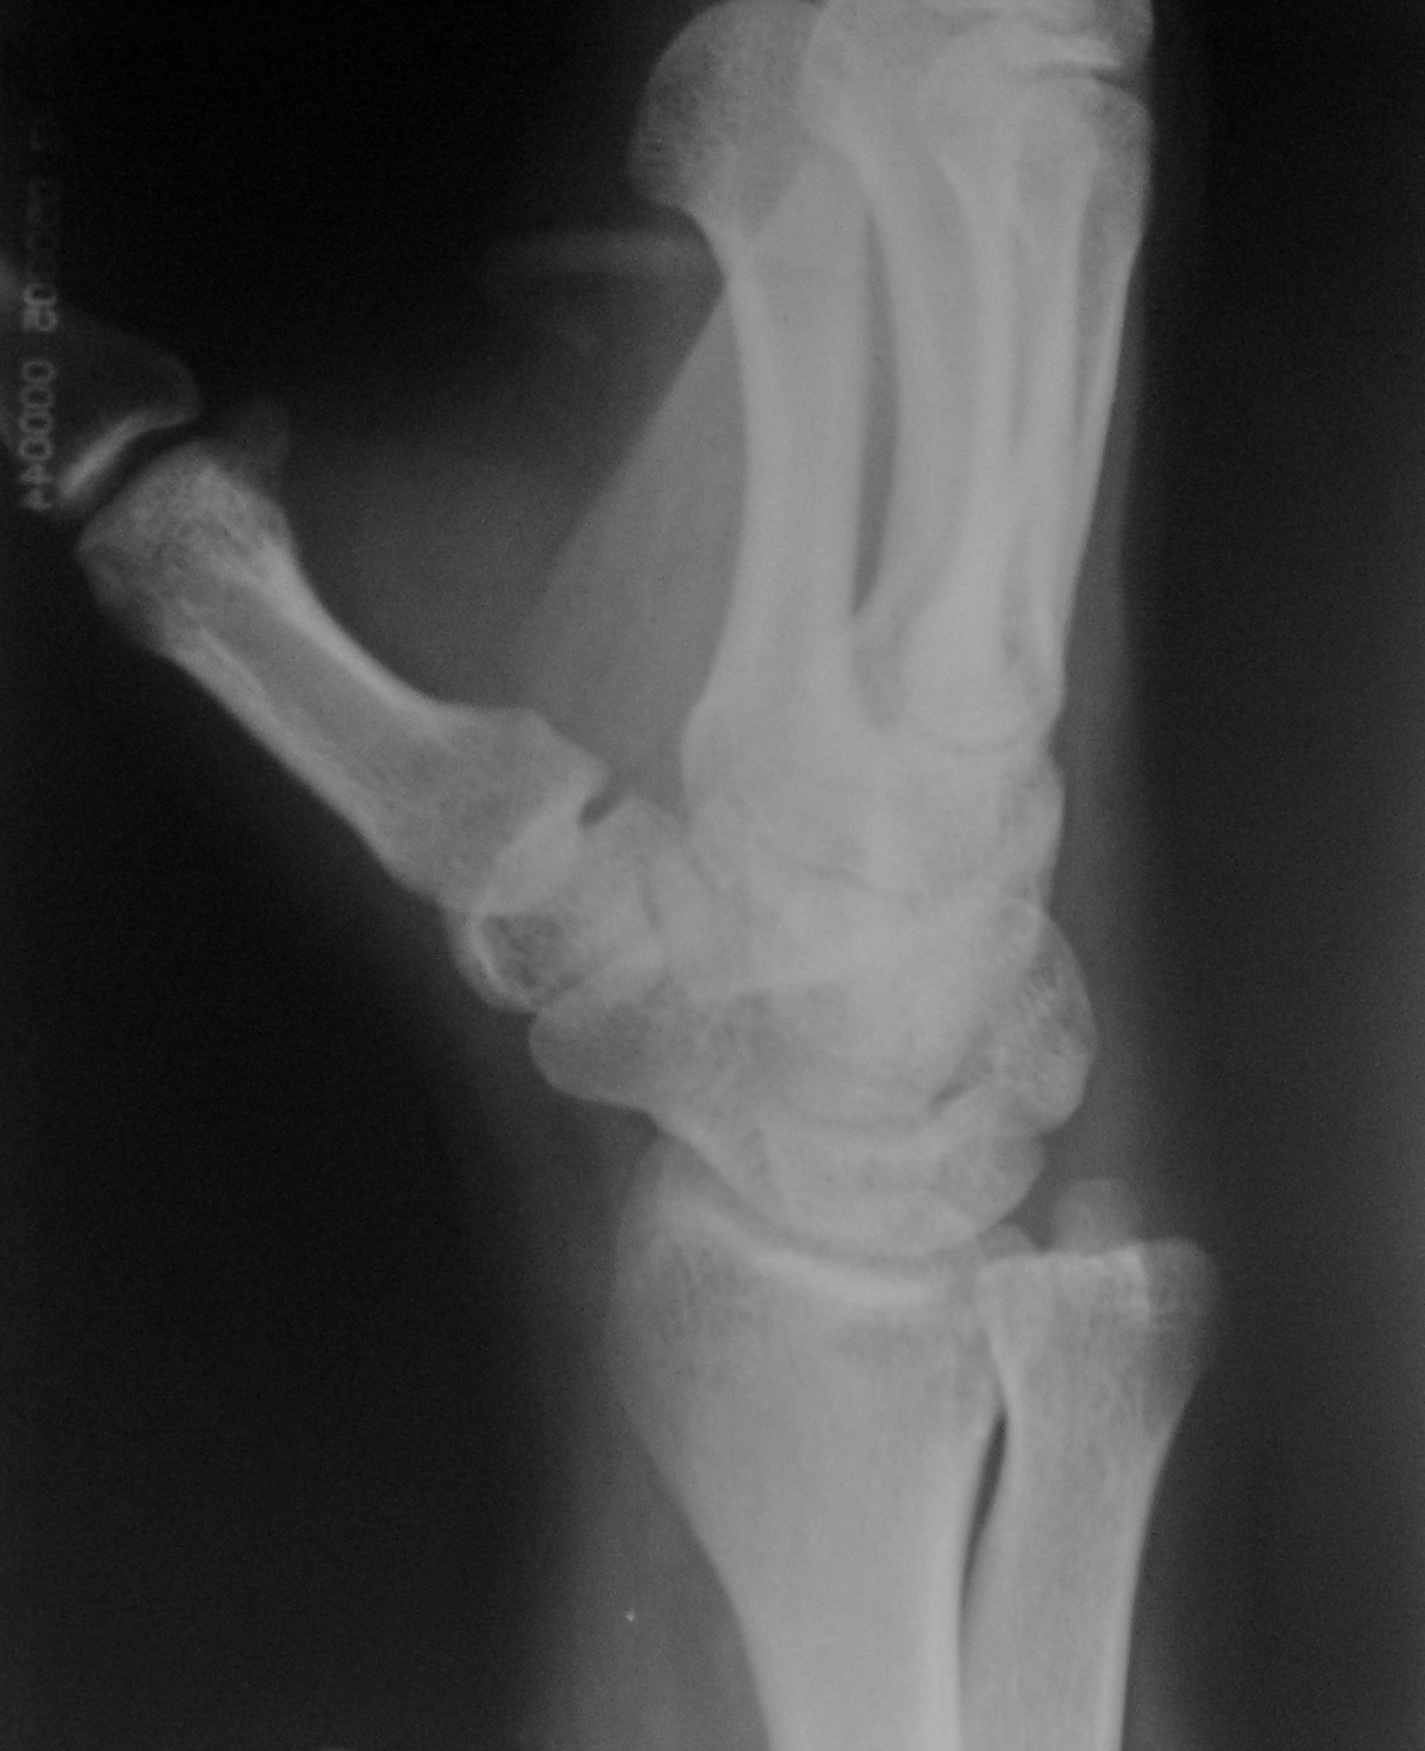

Случай № 1. Травма. Пациент направлен в рентгеновский кабинет врачом хирургом для рентгенографии лучезапястного сустава. Случай № 2. Пациент направлен на рентгенографию голеностопного сустава...

Тип: Клиническое наблюдение

Область: Скелетно-мышечная система

Модальность: Rg

Дата: 12.01.2010 - 16:43